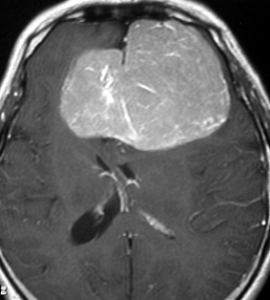

典型的な髄膜腫

この髄膜腫は中程度の大きさのものです。円蓋部髄膜種という最も多い最も手術の簡単なタイプです。麻痺や失語症やてんかんなどの症状はありません。とても美しくて若い女性の髄膜腫でしたが,子供に遺伝はしませんし,癌などと違ってタバコなどこれといった原因がなくて発生するものです。

MRIでの髄膜腫の見え方は撮影の仕方によっていろいろです。左からT1強調画像,T2強調画像,フレア画像といいます。腫瘍の横に小さく白い領域がありますが,これは脳の腫れた部分で脳浮腫といいます。髄膜腫があると周囲に脳浮腫が生じることがあります。

最も見やすいのが,ガドリニウム造影剤を注射して撮影するものです。一般的に髄膜腫は造影剤で白く映し出されます。この腫瘍は左脳側にあります。MRIの軸面という輪切りの写真では左右が逆になりますから注意してください。脳を下から見た図になっています。MRIはいろいろな方向から腫瘍を見ることができますが,右は冠状断という正面から見た図です。よく見ると腫瘍の上と下のはじっこに線状に糸を引いたように造影される部分があります。これをテールサイン(しっぽのサイン)といいます。腫瘍が硬膜に沿って延びている可能性があることを示しています。